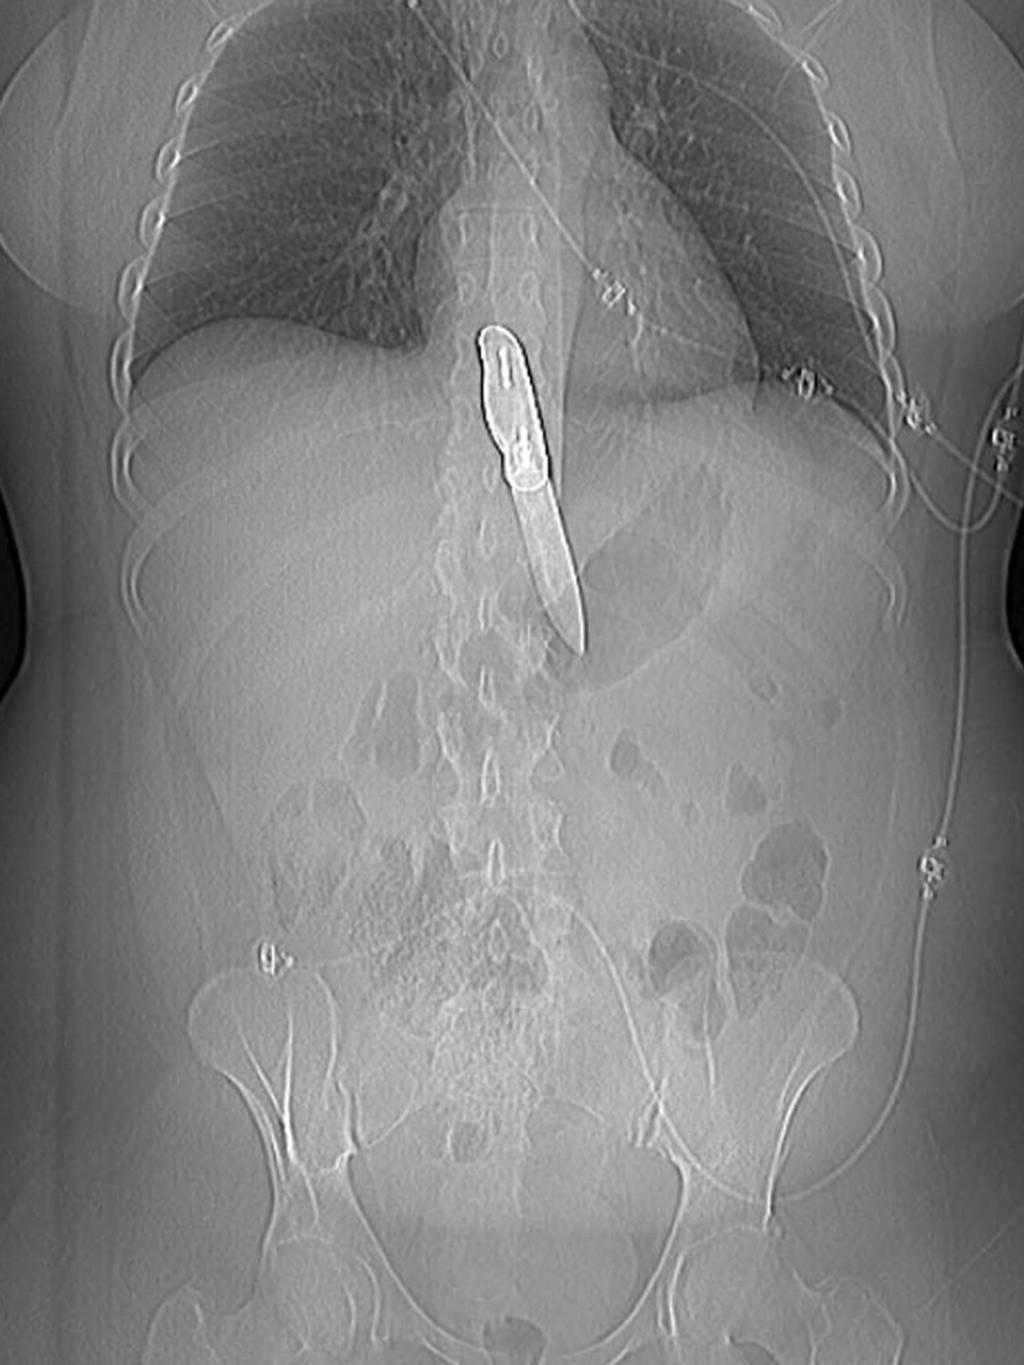

Рентгеновский эффект создает фантастические композиции в этих фотографиях девушки, чье тело становится прозрачным, демонстрируя скелет и внутренние органы. Она позирует в разных позах, ее силуэт светится загадочным свечением. Каждый кадр передает атмосферу научной фантастики и медицинского искусства. Ее кожа кажется полупрозрачной, позволяя увидеть кости и мышцы. Фотографии рассказывают о хрупкости человеческого тела и его внутренней красоте. Девушка то стоит в задумчивости, то делает грациозное движение. Эти иллюстрации вдохновляют на размышления о человеческой анатомии и уязвимости. Каждая картинка - это момент прозрения, когда внешнее уступает место внутреннему. Девушка воплощает образ современной Медузы, сочетающей красоту и загадочность.